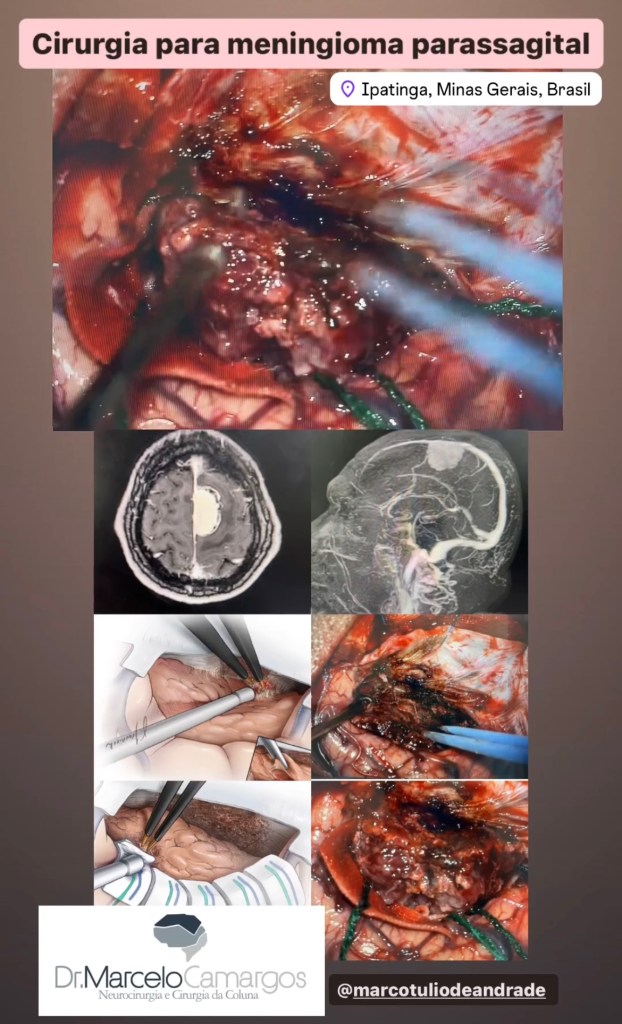

GALERIA De cirurgias

Abaixo você pode conferir imagens de algumas cirurgias já realizadas por Dr. Marcelo Camargos. Caso tenha alguma dúvida ou interesse, não deixe de fazer contato para maiores esclarecimentos!

referência para milhares de pacientes em tratamentos de alta delicadeza e complexidade